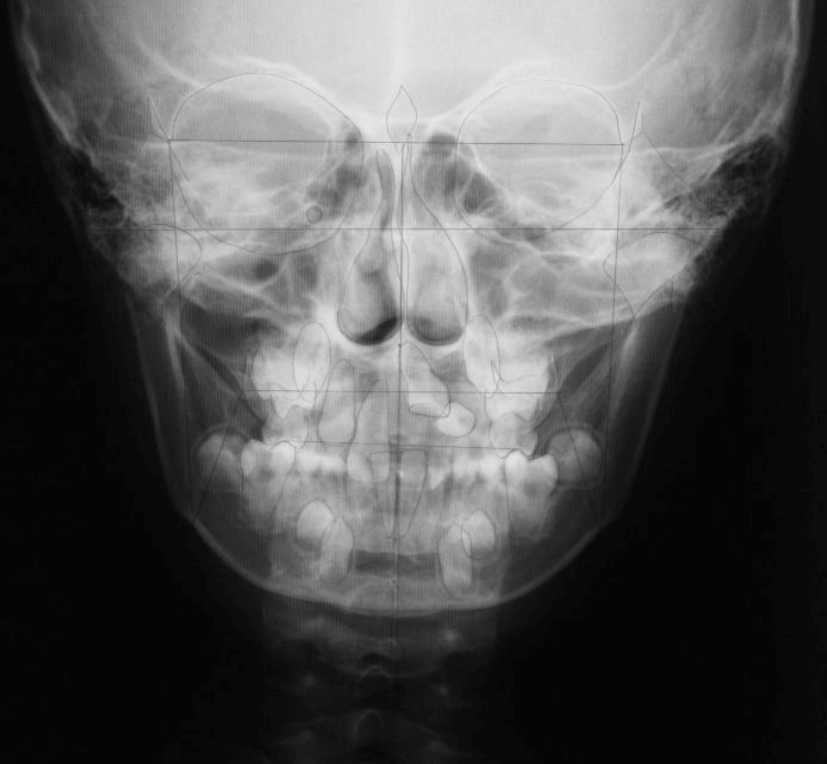

STEP2 精密検査

カウンセリング後、本格的に治療を進めるために精密検査に移ります。より詳しい口腔内の検査、顔・口内の写真撮影、レントゲンやCT撮影、歯型取りが具体的な内容です。顎の骨の歪みをはじめ、骨格的な問題が無いかも診察します。

診断結果 | 8歳3か月の男児。 左上1番(中切歯)と左上2番(側切歯)が埋伏し、発育方向にも異常が認められました。加えて、一部先天性欠如も確認されており、歯列全体の成長に影響を及ぼす可能性があると診断されました。 |

治療内容 |